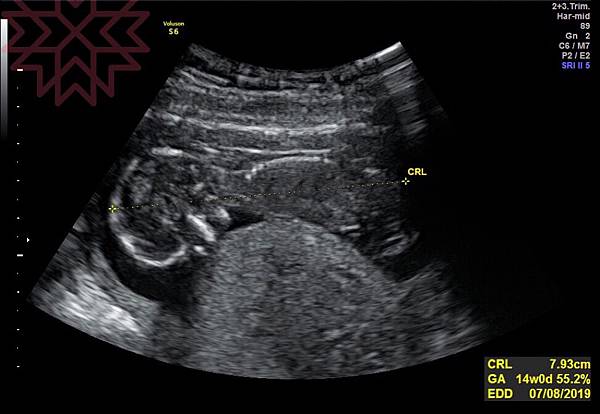

雖然診所位於內湖,但也沒有離我們很遠,到達診所因為有專屬停車場,這一點就贏過了之前產檢的婦產科。禾馨和李木生相同點為整棟大樓都為診所所有,沒有閒雜人等進出,也因為這個原因所以當初沒有選擇大醫院。禾馨民權整體的空間很寬廣,但是等待在診的人數也是非常的多。因為今天沒有指定醫師,所以於櫃檯旁的機器抽取號碼牌後,到號碼時到櫃台先填寫初診單,然後安排看診醫生,再到旁邊的診療區由護理人員量血壓、體重和驗尿蛋白,初步的檢查完後就到這間門等帶看診。等了30分鐘左右就到我們進診間,除了醫師和一位護理人員外,沒有看到其他的人在診間,相對的就不會聽到別人的看診過程。今天的醫師是薛亞蓮醫師,非常的親切,講話好溫柔,因為沒有特別的問題所以直接做例行的超音波檢查,照超音波時非常的仔細,讓我們看了寶寶的長度,頭圍,手腳的骨頭,並告知之後產檢會比較以頭圍為主,不會再另外告知寶寶的長度囉。原本想嘗試看看寶寶的性別,但今天寶寶很害羞的趴著不讓我們看,只能等下次產檢在揭曉。因為還是嚴重脹氣,會導致想吐,所以還是有開一些消脹氣的藥並告知都是孕婦可以安心使用的藥品,不用擔心。看診完就到外面機器抽取繳費的號碼牌,到號繳費時,可以選擇現金或信用卡。繳費後若有需要拿藥,在到領藥櫃檯,藥劑師會核對開立的藥品及告知使用方式。愉快又快速的看診經驗結束。就這樣決定會固定於禾馨民權產檢,也會在此生產。

下面為寶寶今天趴著的特寫,有乖乖長大喔。